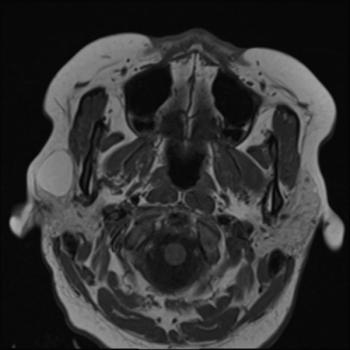

Patient presents with right facial swelling.